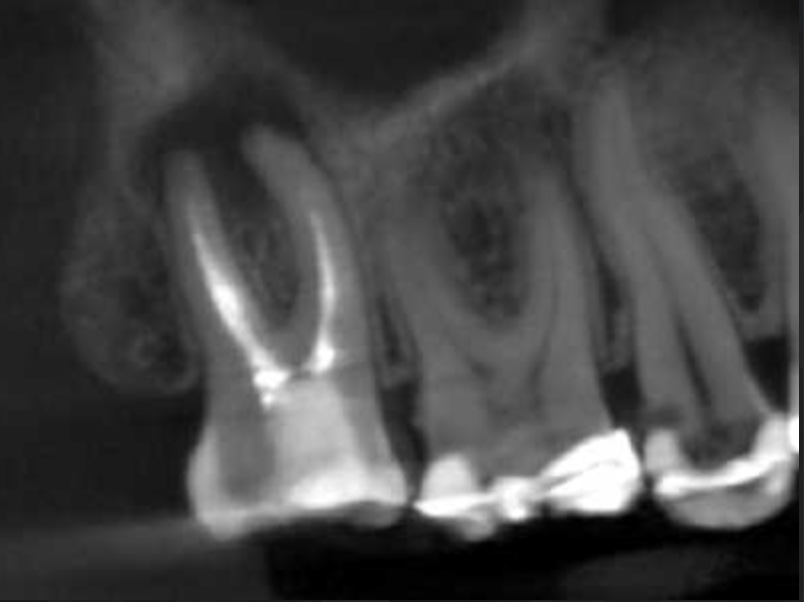

Molar inferior, conducto CM

Molar inferior, conducto MC, Reeco prendo